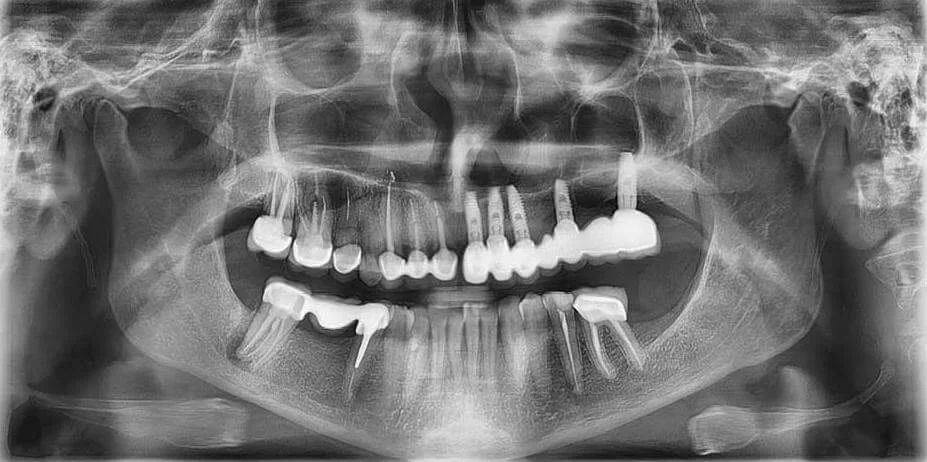

1. Есть ли на снимке признаки воспаления в области верхушек корней зубов?

2. Наблюдаются ли ретенированные или дистопированные зубы?

3. Каково состояние костной ткани вокруг зубов — есть ли признаки резорбции или кисты?

4. Присутствуют ли патологические изменения в височно-нижнечелюстном суставе?

5. Есть ли металлические конструкции или инородные тела, их состояние и влияние на окружающие ткани?